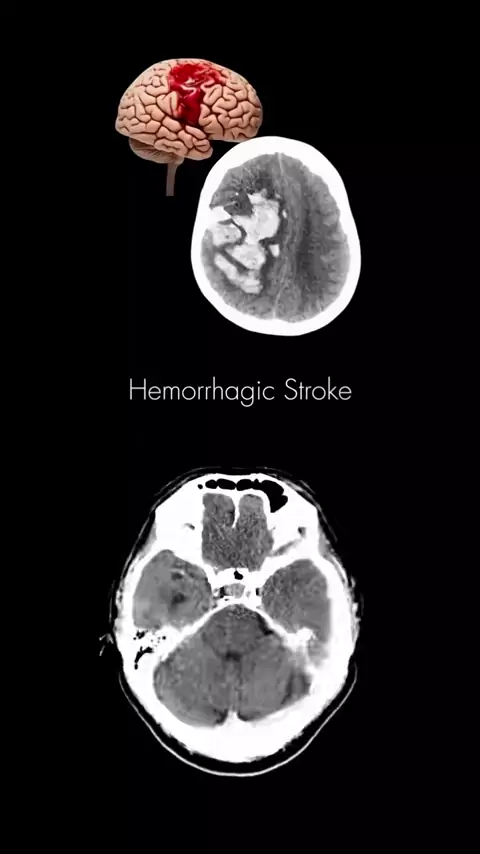

Like save & Share!! Some (CT BRAIN Findings) #anatomy #radiology #ctscan

#stroke #hipertensi #radiologi #ctscan #radiografer

BANTU SHARE BILA ADA KELUARGA YANG HIPERTENSI - SEBAGAI EDUKASI Video: Gambaran pecahnya pembuluh darah di otak karena tekanan darah yang tidak terkontrol - tidak mengkonsumsi obat hipertensi secara rutin padahal dokter sudah memberikan instruksi. KALAU DIMINUM NANTI GINJALNYA MALAH YANG BERMASALAH!?? Hipertensi atau tekanan darah tinggi menjadi penyakit yang mengintai masyarakat Indonesia. Hipertensi meningkatkan risiko penyakit jantung, stroke, gagal ginjal, dan penyakit lainnya yang menyeba...